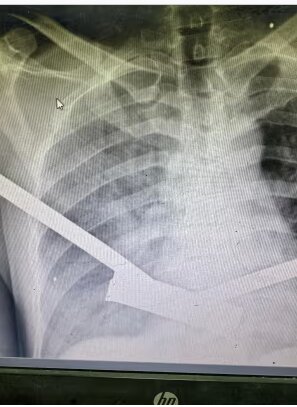

یک پزشک اورژانس آمریکایی که اکنون در مرکز غزه کار می کند گفت که پزشکان همچنان به درمان زخم های عمیق نافذ ایجاد شده توسط قطعات خرد شده ادامه می دهند. دکتر گفت که او به تازگی روی کودکی کار کرده است که قلب و رگ های خونی اصلی اش زخمی شده و خون بین دنده ها و ریه هایش جمع شده و تنفس را دشوار کرده است.

دکتر ادوسومیلی پسر شش ساله ای را که پس از حمله موشکی اسرائیل به چادری که خانواده اش در آن زندگی می کردند، به بیمارستان رساند. می گوید: کودک زخم های سوراخ سوزنی داشت که هیچ نشانه ای از مقیاس آسیب زیر پوست نداشت. من مجبور شدم شکم و سینه اش را باز کنم. او پارگی هایی در ریه، قلب و سوراخ هایی در سراسر روده داشت. مجبور شدیم همه چیز را تعمیر کنیم. او خوش شانس بود که یک تخت در بخش مراقبت های ویژه وجود داشت. اما با وجود این، آن پسر جوان دو روز بعد فوت کرد.»